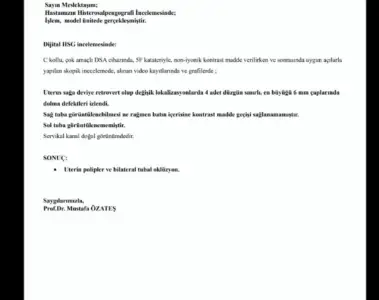

Tüplerin açık gibi görünüyor.Merhabalar bende bugün rahîm filmi cektirdim ama henüz sonuçları göstermedim anlayan varsa bakabilirr mi

Bende anestezili çektiricem korkuyorum biraz rahim filmi konusunda bilgim yokBugün anestezi almadan çektirdim. Çok zor geçti. 5,6 kez deneme yapıldı sıvı maddenin tüplere geçişi olmadı bi türlü. Sonucumu aldım. Bilgisi olan varsa rica etsem yorumlayabilir mi.